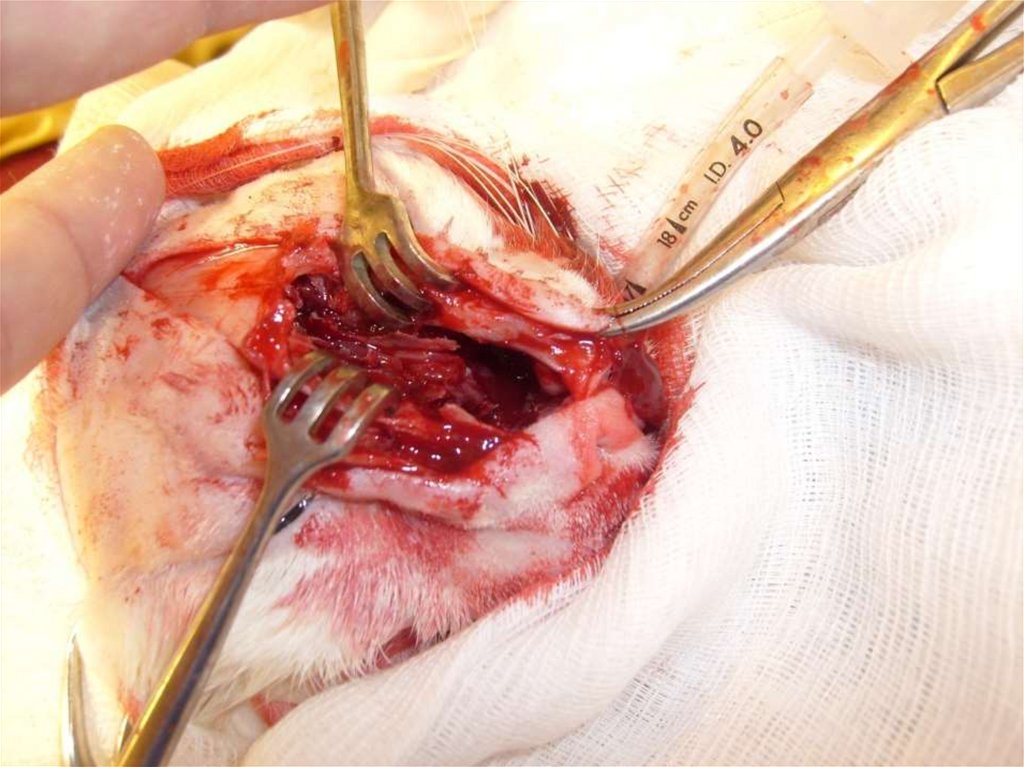

• Ринотомия-вскрытие полости носа

и лобных пазух.

Ринотомия.

• Перед операцией проводят лигирование сонной

артерии.

• Вскрытие полости носа и лобной пазухи.

• Надкостницу рассекают по средней линии, а затем

рассекают кость при помощи долота или

осциллирующей пилы. Кость разводят латерально.

• Удаляют носовую перегородку и носовые раковины.

• После проведения необходимых манипуляций

костную пластинку возвращают на место и

фиксируют швом накладываемым на надкостницу.

Костный распил.